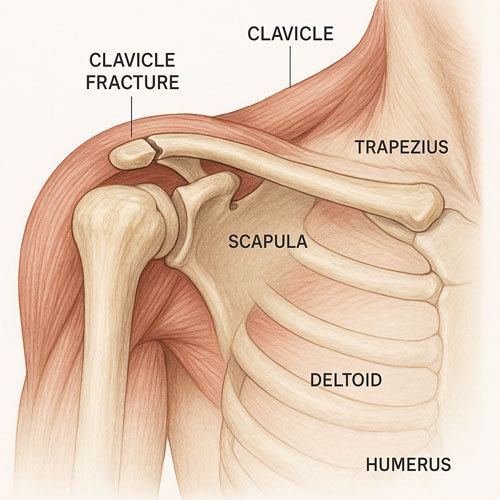

شکستگی کنار مفصل شانه

درمان جراحی شکستگی ترقوه زمانی مطرح میشود که شکستگی دارای جابجایی زیاد، قطعات خرد شده یا خطر آسیب عروقی و عصبی باشد. این روش بیشتر در شکستگی انتهای خارجی یا نزدیک مفصل ها کاربرد دارد. جراحی با هدف ثابت کردن قطعات استخوان با استفاده از پلیت، پیچ یا گاهی میله داخل استخوانی انجام می شود. این تثبیت موجب بازگشت سریع تر عملکرد شانه و کاهش خطر جوش خوردن ناقص می گردد. پس از عمل، استفاده موقت از اسلینگ، مراقبت از زخم جراحی و شروع زودهنگام توان بخشی، بخش مهمی از فرایند بهبودی را تشکیل می دهند. انتخاب جراحی باید بر اساس ارزیابی دقیق پزشک، نوع شکستگی و نیازهای حرکتی بیمار انجام گیرد تا بهترین نتیجه عملکردی و کاهش ریسک عوارض حاصل شود.